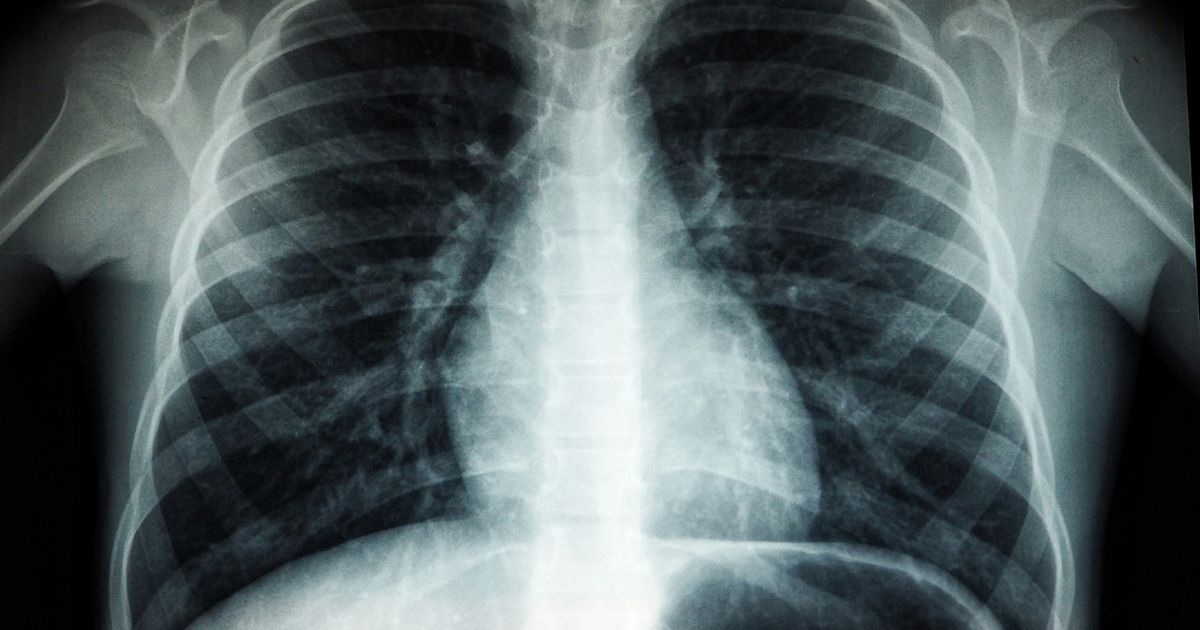

A new study by Duke researchers marked a major shift in

understanding one of the deadliest forms of lung cancer.

SCLC makes up 10 to 15% of all lung cancers, according to

the American Cancer Society, with about 30,000 diagnoses every year.

The cancer is known for growing faster than other types and

has often spread to other parts of the body before it is diagnosed. The ACS

reports that the SCLC 5-year survival rate is less than 10%, due to its

aggressive nature.